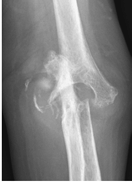

Figure 62-8 A:

Preoperative radiograph of a typical patient, a 47-year-old right hand–dominant man with right elbow osteoarthritis, demonstrates osteophyte formation and joint space narrowing. B: Postoperatively, the osteophytes and bony spurs have been removed. |

anterior and posterior aspects of the elbow joint can be visualized and

pathology addressed (Fig. 62-8). To obtain a